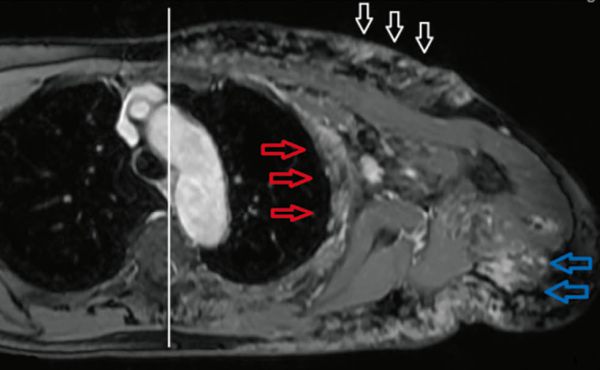

Laparoskopische Cholezystektomie für symptomatische Cholezystolithiasis (CCL) bei „Kasabach-Merritt-Syndrom“ (KMS)